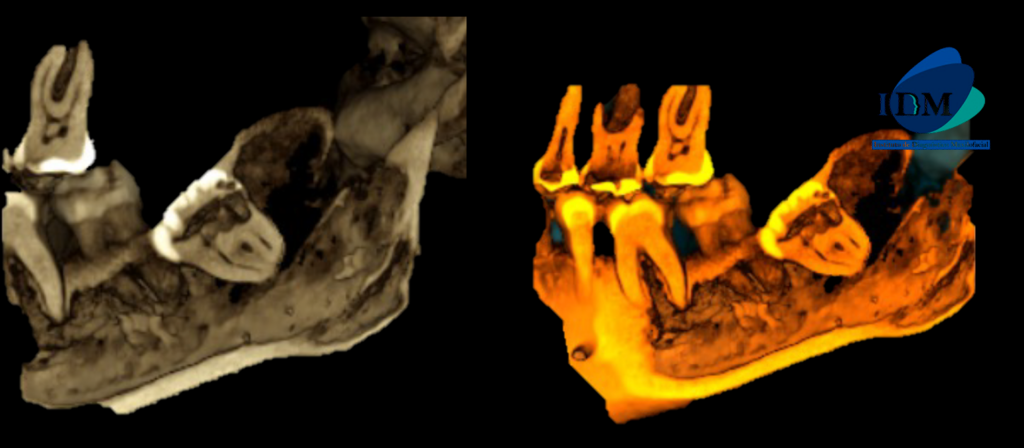

En la reconstrucción 3D se representa la reabsorción de la pieza 38 (Figura 4)

RECONSTRUCCIÓN 3D